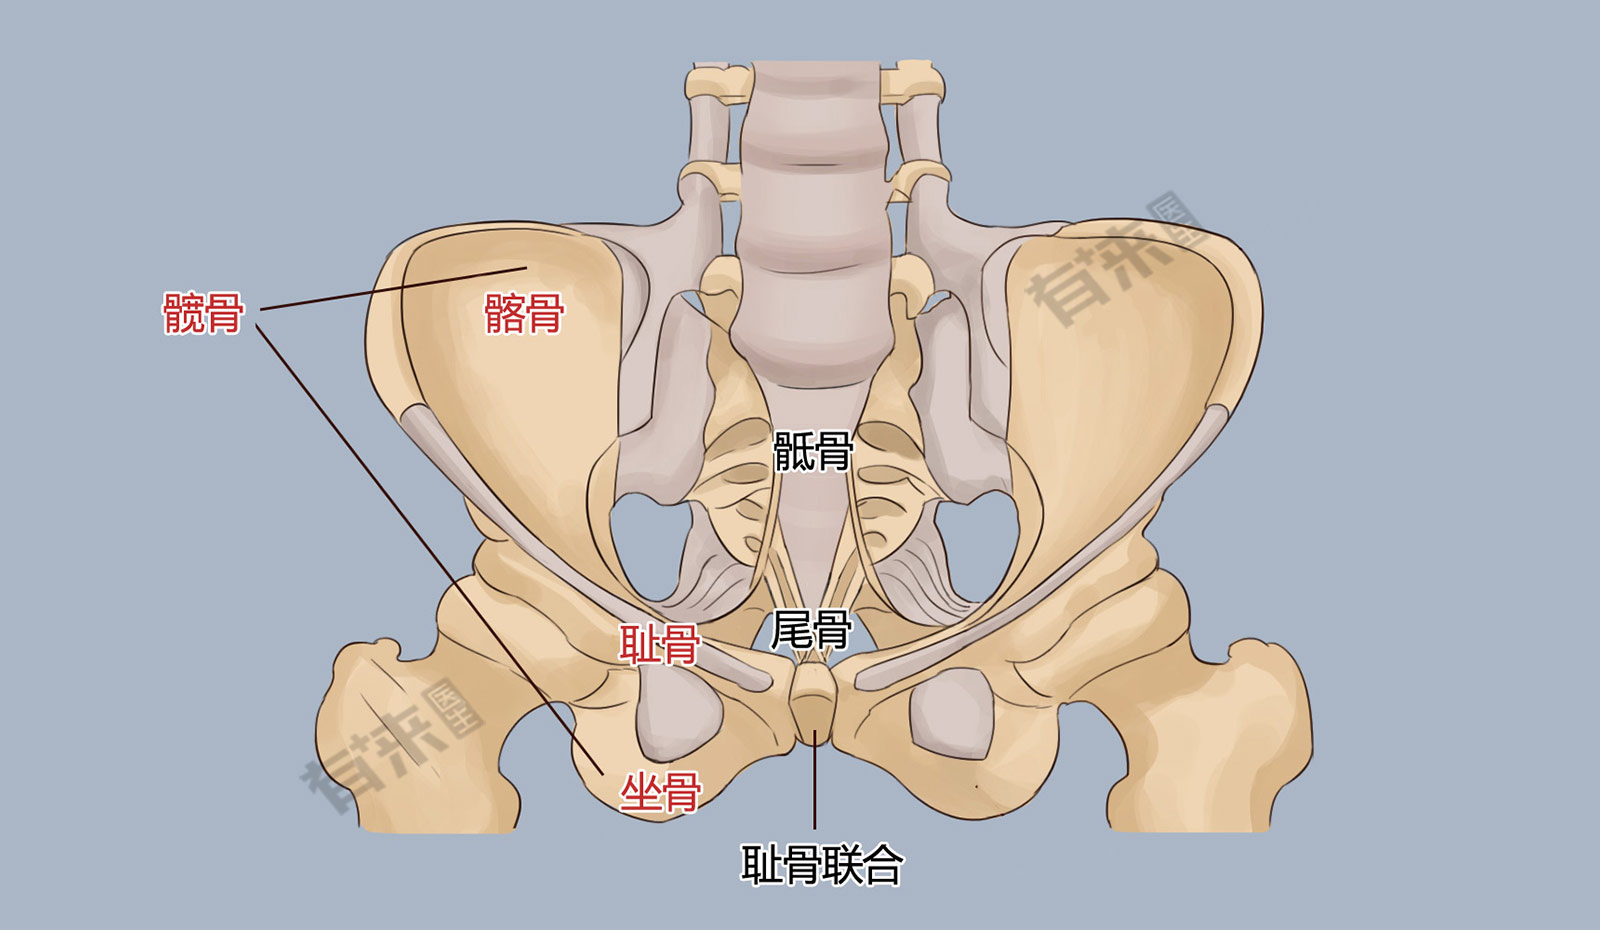

胯骨图片

髋骨_有来医生

正常髋骨解剖示意图-人体解剖图

骨骼日记之髋骨 简介: 髋骨为不规则骨,由髂骨,耻